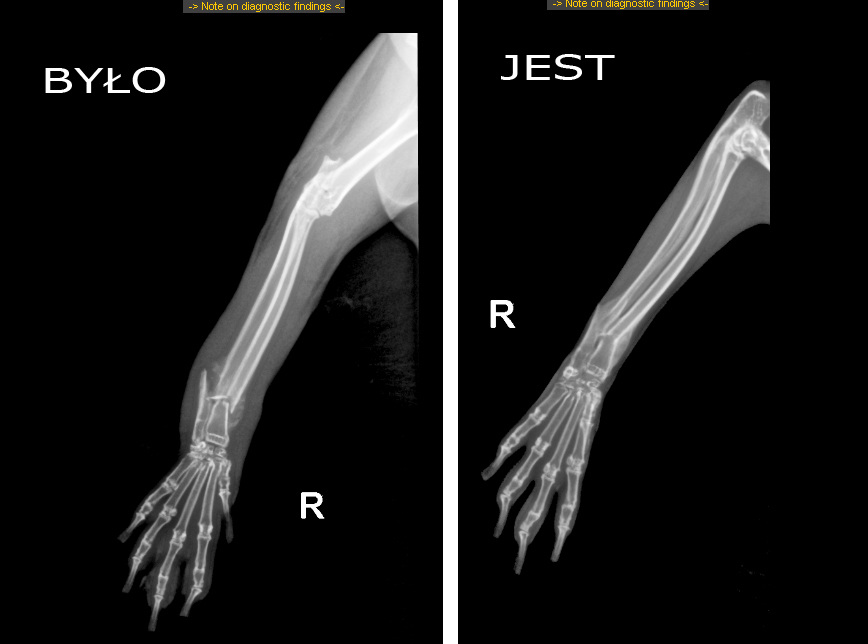

dopiero do mnie dotarło, że te takie białe mazy na zdjęciu RTG to futerko #Kefirka.i.

Pobierz obrazek (132.5kiB)

no to możemy wznieść toast sokiem z marchewki. łapka #Kefirka.i się zrosła.

Pobierz obrazek (1154.0kiB)

skierowanie na rtg jest. więc w środę dowiemy się, jak się mają kosteczki w łapce #Kefirka.i. czy wiecie, że drut używany do spajania kości króliczych ma 0,7-0,9 mm, bo te kosteczki są takie cienkie